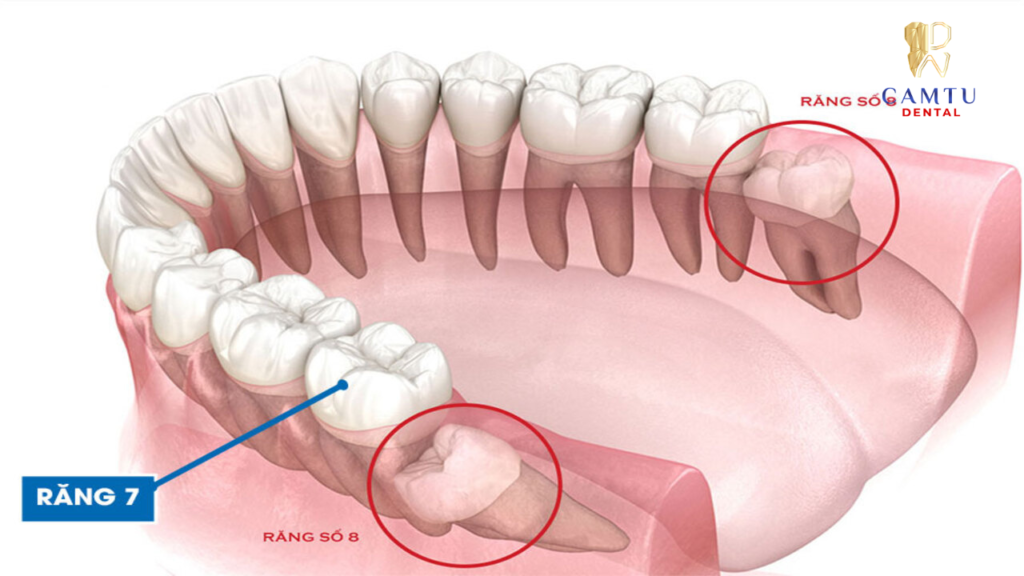

Răng số 7 là răng cối lớn thứ hai trên mỗi cung hàm, nằm ngay phía trước răng số 8 (răng khôn) và phía sau răng số 6. Một người trưởng thành thường có tổng cộng 4 răng số 7, phân bố đều ở hai hàm trên và dưới. Đây là nhóm răng vĩnh viễn mọc khá sớm, thường xuất hiện trong độ tuổi khoảng 12 đến 13 và tồn tại lâu dài trong suốt quá trình ăn nhai.

Về cấu trúc, răng số 7 có thân răng lớn với nhiều múi nhai và chân răng chắc chắn, giúp chịu lực nhai mạnh. Nhờ diện tích mặt nhai rộng, răng này có khả năng nghiền nhỏ thức ăn hiệu quả trước khi được nuốt xuống dạ dày, góp phần hỗ trợ hệ tiêu hóa hoạt động tốt hơn.

Ngoài chức năng ăn nhai, răng số 7 còn đóng vai trò quan trọng trong việc duy trì sự ổn định của cung hàm và khớp cắn. Nếu răng số 7 bị mất mà không được phục hình kịp thời, các răng kế cận có thể dịch chuyển vào khoảng trống, răng đối diện trồi lên, từ đó gây lệch khớp cắn và làm giảm hiệu quả nhai của toàn hàm.